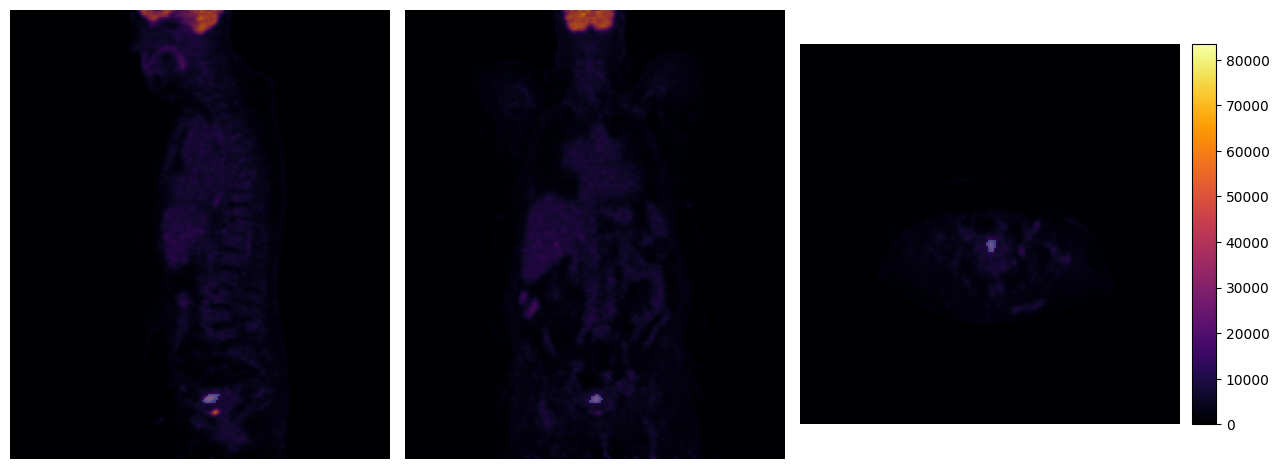

[3]:

vmin, vmax = image.min()[0], image.max()[0]

interact(

mpr_plot,

image=fixed(image),

labels=fixed(labels[0]),

x=IntSlider(112, 0, 191),

y=IntSlider(104, 0, 191),

z=IntSlider(195, 0, 226),

vmin=IntSlider(4000, vmin, vmax, 100),

vmax=IntSlider(36000, vmin, vmax, 100),

label_alpha=FloatSlider(0.7, min=0.0, max=1.0, step=0.1),

continuous_update=False

)

None

[11]:

mpr_plot(pet[0], labels=tumor_mask[0], y=100, z=195)

../../_images/tutorials_imfusion-sdk_1_working_with_images_22_0.png